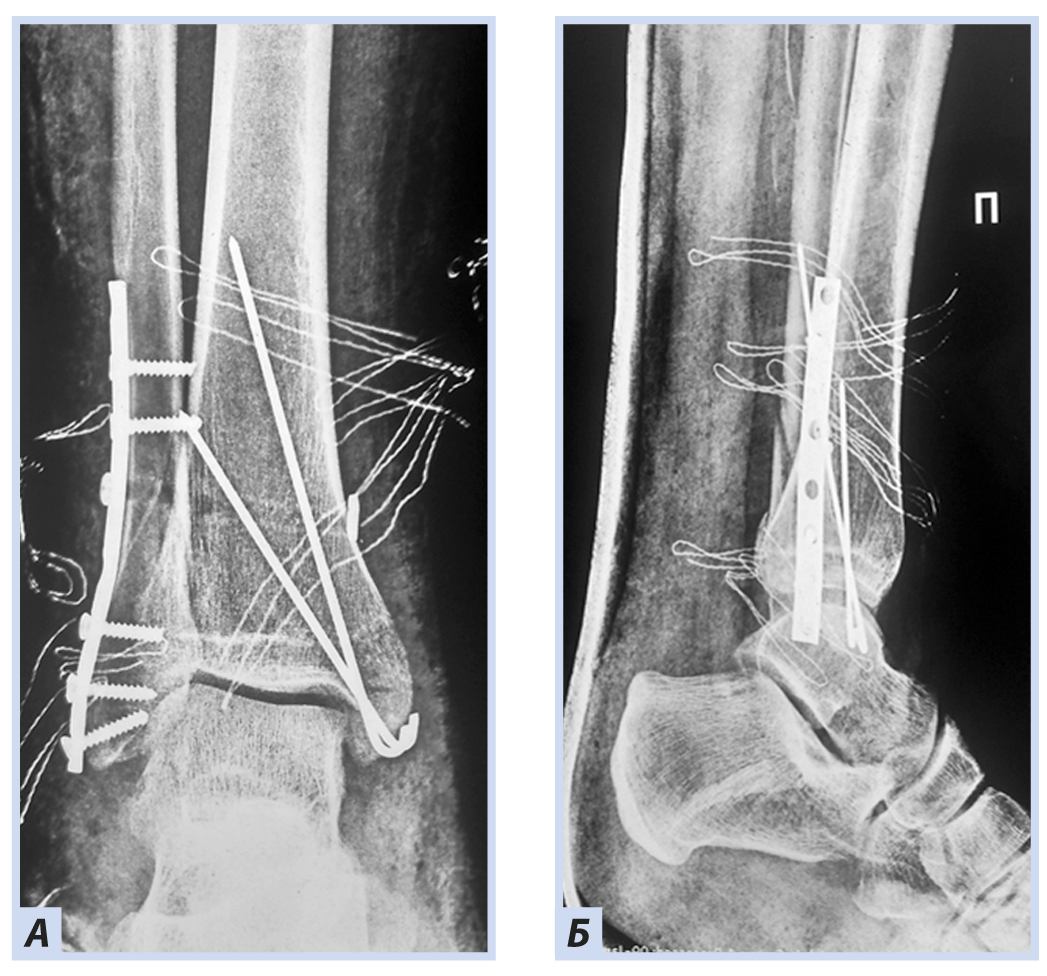

У детей третьей возрастной группы было частичное или полное физиологическое закрытие зоны роста, и ее повреждение встречается гораздо реже, травма становится похожей на взрослую, классификация Solter–Harris теряет свою актуальность. У 5 пациентов данной возрастной группы было выявлено сочетание перелома медиальной лодыжки и диафизарного перелома малоберцовой кости выше уровня синдесмоза. Эти переломы нестабильные, так как происходят по сценарию пронационно эверсионного механизма травмы. При постановке диагноза пациентам с закрытыми зонами роста необходимо использовать классификации Danis–Weber и Lauge–Hansen [15]. Капсула сустава и связочный аппарат становятся более ригидными, и отсутствие дополнительной фиксации может привести к их неполному восстановлению. Динамический компрессионный остеосинтез медиальной лодыжки по Weber позволил начать раньше реабилитационные мероприятия, и функция конечности у таких пациентов была полностью восстановлена через 6 нед. с момента перелома. В случаях остеосинтеза спицами нагрузочный режим был более щадящим, поэтому восстановление функции наступило в течение 8 нед. Неудовлетворительных результатов в этой группе больных не было.

Клиническое наблюдение 3

Мальчик, 16 лет, диагноз «Закрытый перелом обеих лодыжек правого голеностопного сустава с подвывихом стопы кнаружи. Супинационно-эверсионный механизм травмы». Травма получена в результате падения на льду. По данным ультразвуковой диагностики был диагностирован частичный разрыв передней порции дистального межберцового синдесмоза. Выполнен остеосинтез внутренней лодыжки спицами, дистальный межберцовый синдесмоз фиксирован синдесмозной системой (Arthrex Tightrope Ankle), перелом латеральной лодыжки фиксирован 1/3 трубчатой пластиной. Внешняя иммобилизация осуществлена гипсовой лонгетой. Контрольная рентгенография и исследование микроциркуляции в области перелома методом лазерной допплеровской флоуметрии выполнены через 8 нед. после операции. На рентгенограммах имеются признаки зажившего перелома, по данным флоуметрии наблюдается активация капилляризации тканей и нутритивного кровотока в условиях регенераторного процесса. Спицы удалены через 8 нед., конфигурация сустава восстановлена полностью (рис. 10–13).

Рис. 10. Мальчик, 16 лет. Рентгенограммы дистального отдела костей правой голени. Перелом обеих лодыжек правого голеностопного сустава с подвывихом стопы кнаружи: А — прямая проекция; Б — боковая проекция.

Рис. 11. Тот же пациент. Ультразвуковoе исследование дистального межберцового синдесмоза. Признаки разрыва передней тибиофибулярной связки.

Рис. 12. Тот же пациент. Рентгенограммы дистального отдела костей правой голени. Остеосинтез малоберцовой кости пластиной, остеосинтез внутренней лодыжки спицами, фиксация синдесмоза системой Arthrex Tightrope Ankle: А — прямая проекция; Б — боковая проекция.

Рис. 13. Тот же пациент. Рентгенограммы дистального отдела костей правой голени через 8 нед. Консолидация костных отломков: А — прямая проекция; Б — боковая проекция.